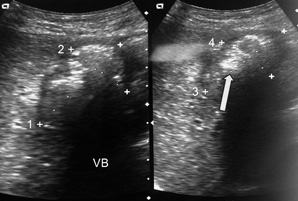

Mujer de 46 años de edad que se presentó a Urgencias en septiembre de 2013 por dolor abdominal intermitente, de 3 meses de duración, así como nauseas, vómitos y pérdida de peso. Era alcohólica y abusaba de metanfetaminas. El examen reveló dolor abdominal difuso sin datos de irritación peritoneal. Los resultados de laboratorio, que incluyeron: enzimas, amilasa, creatinina sérica y electrolitos, fueron normales. El US abdominal fue reportado como cálculo vesicular sin dilatación de vías biliares (figura 1). Las radiografías simples de abdomen no fueron de utilidad diagnóstica. Recibió líquidos intravenosos y antiespasmódicos y fue egresada por alta voluntaria. Acudió a la consulta externa en marzo de 2014 por cólico biliar con el antecedente de ingerir alimentos colecistoquinéticos. Se programó para cirugía laparoscópica electiva. Durante la cirugía se encontraron múltiples adherencias, dificultando el procedimiento, por lo que se decidió cirugía abierta. Se encontró un plastrón formado por una vesícula escleroatrófica, epiplón y duodeno con adherencias firmes. Al reconocer el cístico se realizó una colangiografía, encontrando una vía biliar normal. Había leve distensión gástrica. Se practicó una incisión de 6 cm que abarcó la primera porción del duodeno y píloro, así como 2 cm de estómago, observando un cálculo de 2.5 cm, el cual fue extraído (figura 2). Debido al gran proceso inflamatorio, se valoró el riesgo de fistulización por la sutura, por lo que se decide resección de antro, píloro y 2-3 cm de la primera porción de duodeno con una anastomosis tipo Bilroth 1. La paciente fue egresada en buenas condiciones.